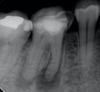

What is shown?

no caries or restos, teeth vital, not apical perio → cemento-osseous dysplasia